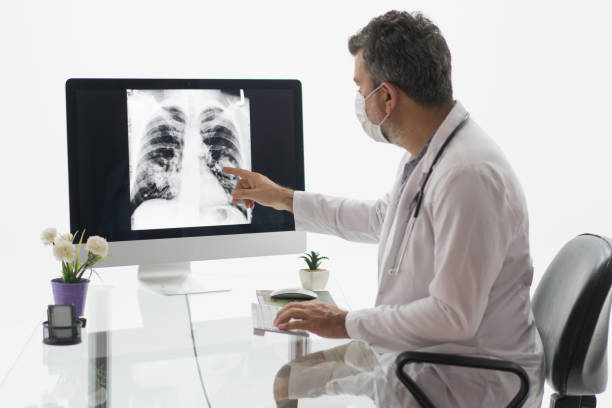

폐암은 초기에는 증상이 미미하거나 없을 수 있습니다. 그러나 조기에 발견하고 진단받으면 치료의 성공률이 훨씬 높아집니다. 초기에 폐암을 발견하면 조기 치료를 시작하여 종양의 성장과 전이를 제한할 수 있습니다. 뿐만 아니라, 치료에 있어 다양한 치료 방법을 활용할 수 있어 폐암 초기 증상을 잘 알고 있는 것이 중요합니다.